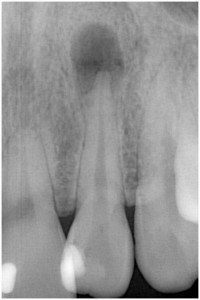

歯髄壊死 左上の前歯 川口の歯科 歯医者 さかえ歯科クリニック

2014年12月16日